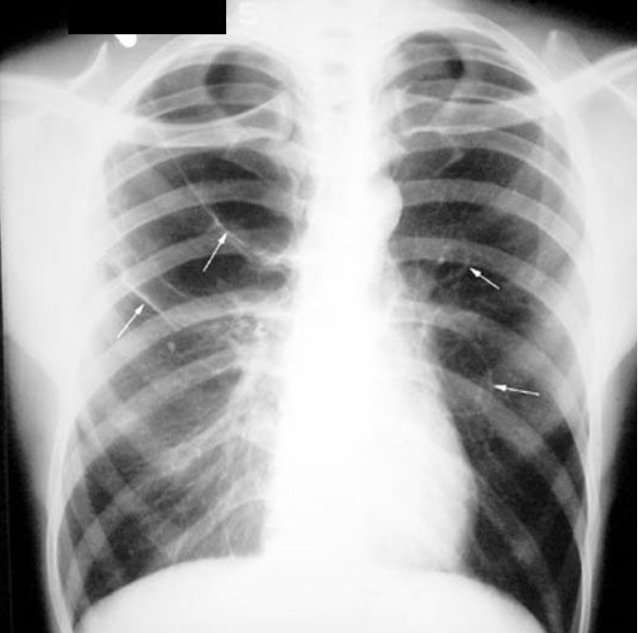

Multiple Cavities

Multiple cavities are seen in hematogenous etiology (metastatic, septic emboli, vasculitis) or bronchogenous etiology (aspiration abscess, tuberculosis, coccidiomycosis), bronchiectasis.